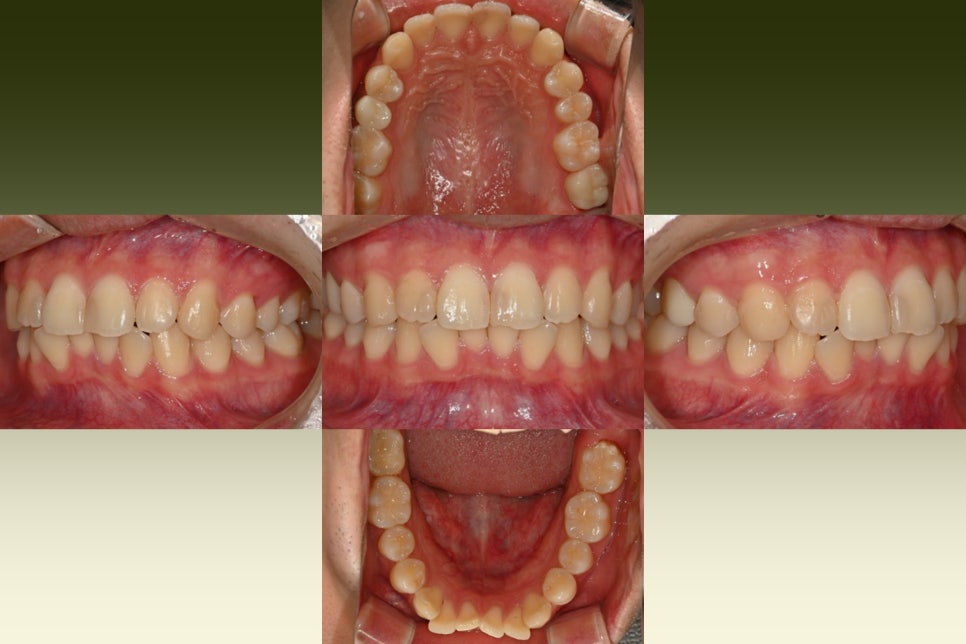

교과서 적으로 충치 범위에 따른

치료방법은 다릅니다.

충치가 있는 부분을 전부 제거하면서

범위가 작은 부분은 레진,

좀 더 진행된 부분은 인레이,

그리고 깊게 썩은

작은 어금니(# 15번) 같은 경우는

신경치료가 고려됩니다.

나머지 어금니 또한 충치를 걷어내고

인레이 와동을 형성한 모습입니다.

인레이 제작 과정에서도 전체적인

치아의 색상, 교합, 인접치아의

연관성을 고려해야 됩니다.